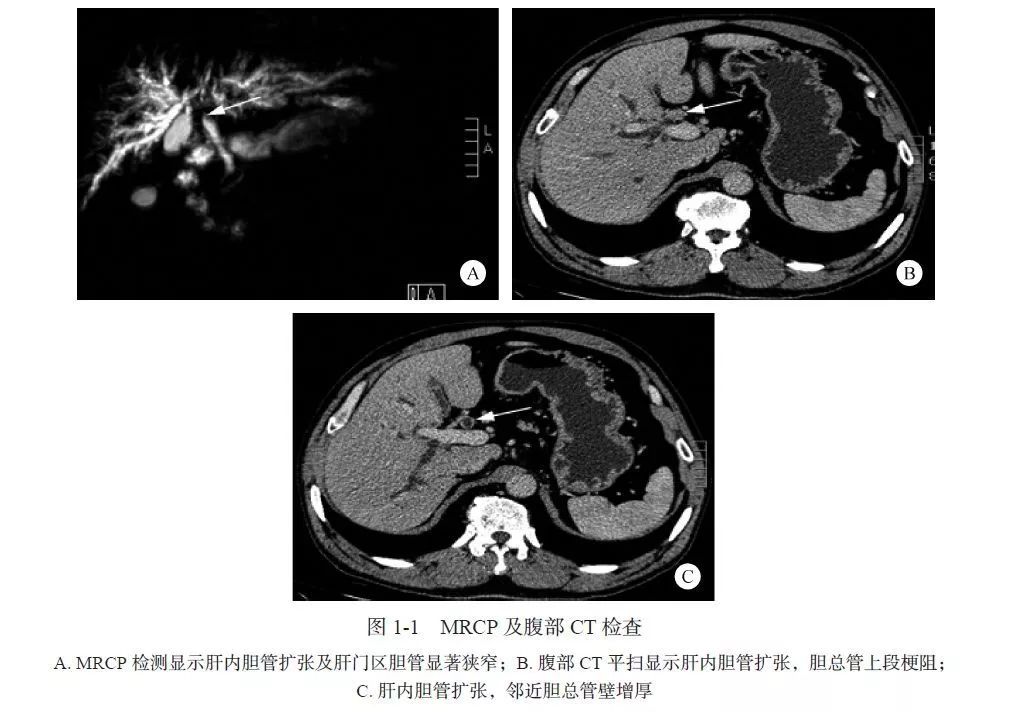

辅助检查:TBil 344.5 μmol/L,ALP 300.5 U/L,AST 658.7 U/L,ALT 646.3 U/L。甲、乙、丙、戊型肝炎病毒抗体均阴性。EB 病毒、巨细胞病毒测定结果阴性。ANA 系列:抗平滑肌抗体(抗-SMA)、抗肝肾微粒体抗体(抗-LKM-1)、抗肝细胞胞质1 型抗体(抗-LC1)、抗肝- 胰抗体/ 抗可溶性肝抗原抗体(抗-SLA/ 抗-LP)均阴性。类风湿因子202 IU/ml(正常值< 15 IU/ml),CA19-9 671.92 U/ml(正常值<37 U/ml)。MRCP 扫描:肝内胆管扩张及肝门区胆管显著狭窄(图1-1A)。腹部CT 平扫:肝内胆管扩张,胆总管上段梗阻(图1-1B、C),邻近胆总管壁增厚(见图1-1C),提示肝门胆管癌(HCCA)可能。